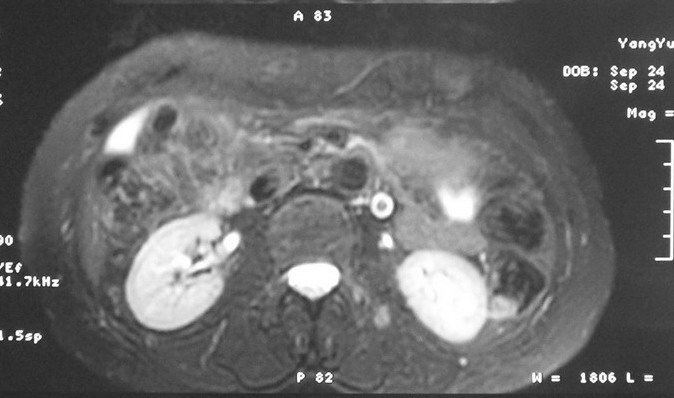

标题: MRI2066:腹膜后占位,请会诊,CT18531近期扫描图像

无明显不适,体检发现,

mri基本排除血管类肿瘤,明显强化说明极富血供,临床无症状,考虑胰岛细胞瘤可能大。

强化明显,并见有血管与之相连;考虑巨淋巴增生症.

极富血供的占位性病变,首先考虑良性,期待结果。